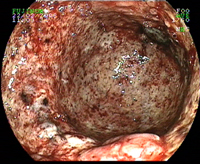

Poussée de rectocolite hémorragique

Ulcères du rectum sur rectocolite hémorragique

Ulcérations coliques de rectocolite hémorragique